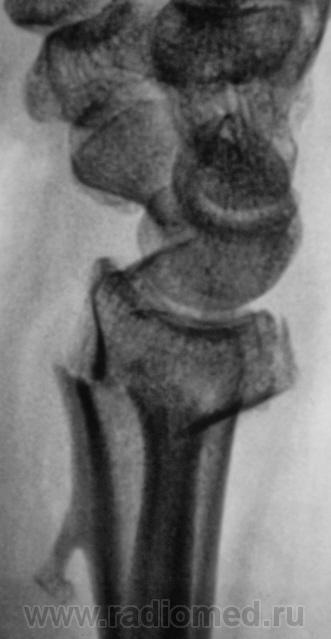

Несросшийся перелом и ложный сустав.

Неблагоприятные местные и общие условия при лечении переломов костей могут в конечном счете привести к отсутствию сращения, то есть к несросшемуся перелому и ложному суставу. это два очень близких понятия. О несросшимся переломе говорят тогда, когда не прошло два срока , необходимыхх для нормального сращения (временной фактор). на ретгенограммах видна щель между отломками, концы их атрофичны, порозны и закруглены. По истечении двойного срока говорят о ложном суставе. Кроме того, ложный сустав имеет четкие морфологические критерии, выявляемые рентгенологически: щель между концами костных отломков, раструбовидная деформация концов их и склероз костномозгового канала. Необходимо отметить, что со временем формируется анатомическое образование, которое очень близко по своему строению к нормальному суставу: имеются суставные поверхности, покрытые хрящом, капсула сустава, суставная щель и жидкость. Ложные суставы и несросшиеся переломы- нередкие и очень серьезные осложнения в лечении переломов костей. Они требуют оперативного лечения с применением металлических фиксаторов. Ложные суставы могут формироваться не только после консервативного, но и после оперативного лечения, о чем будет сказано далее. Однако врачу приходится сталкиваться с ситуацией , когда имплантанты удаленыи имеется ложный сустав. В таких случаях после удаления фиксаторов остаются структурные изменения, которые прослеживаются на рентгенограммах.